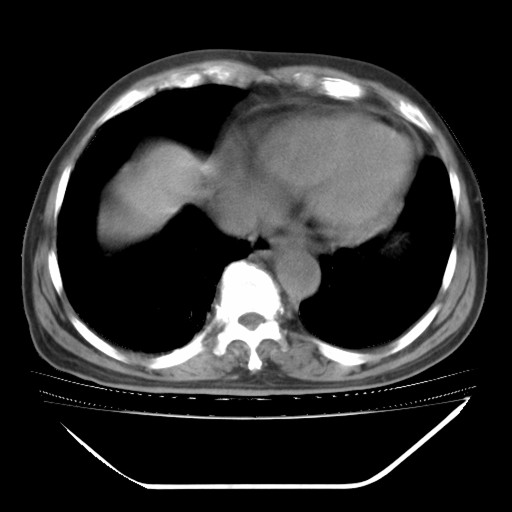

以下是引用hhcckk在2009-5-29 10:34:00的发言:[br]左下肺片絮状边缘模糊影,考虑感染,建议治疗后复查[br]